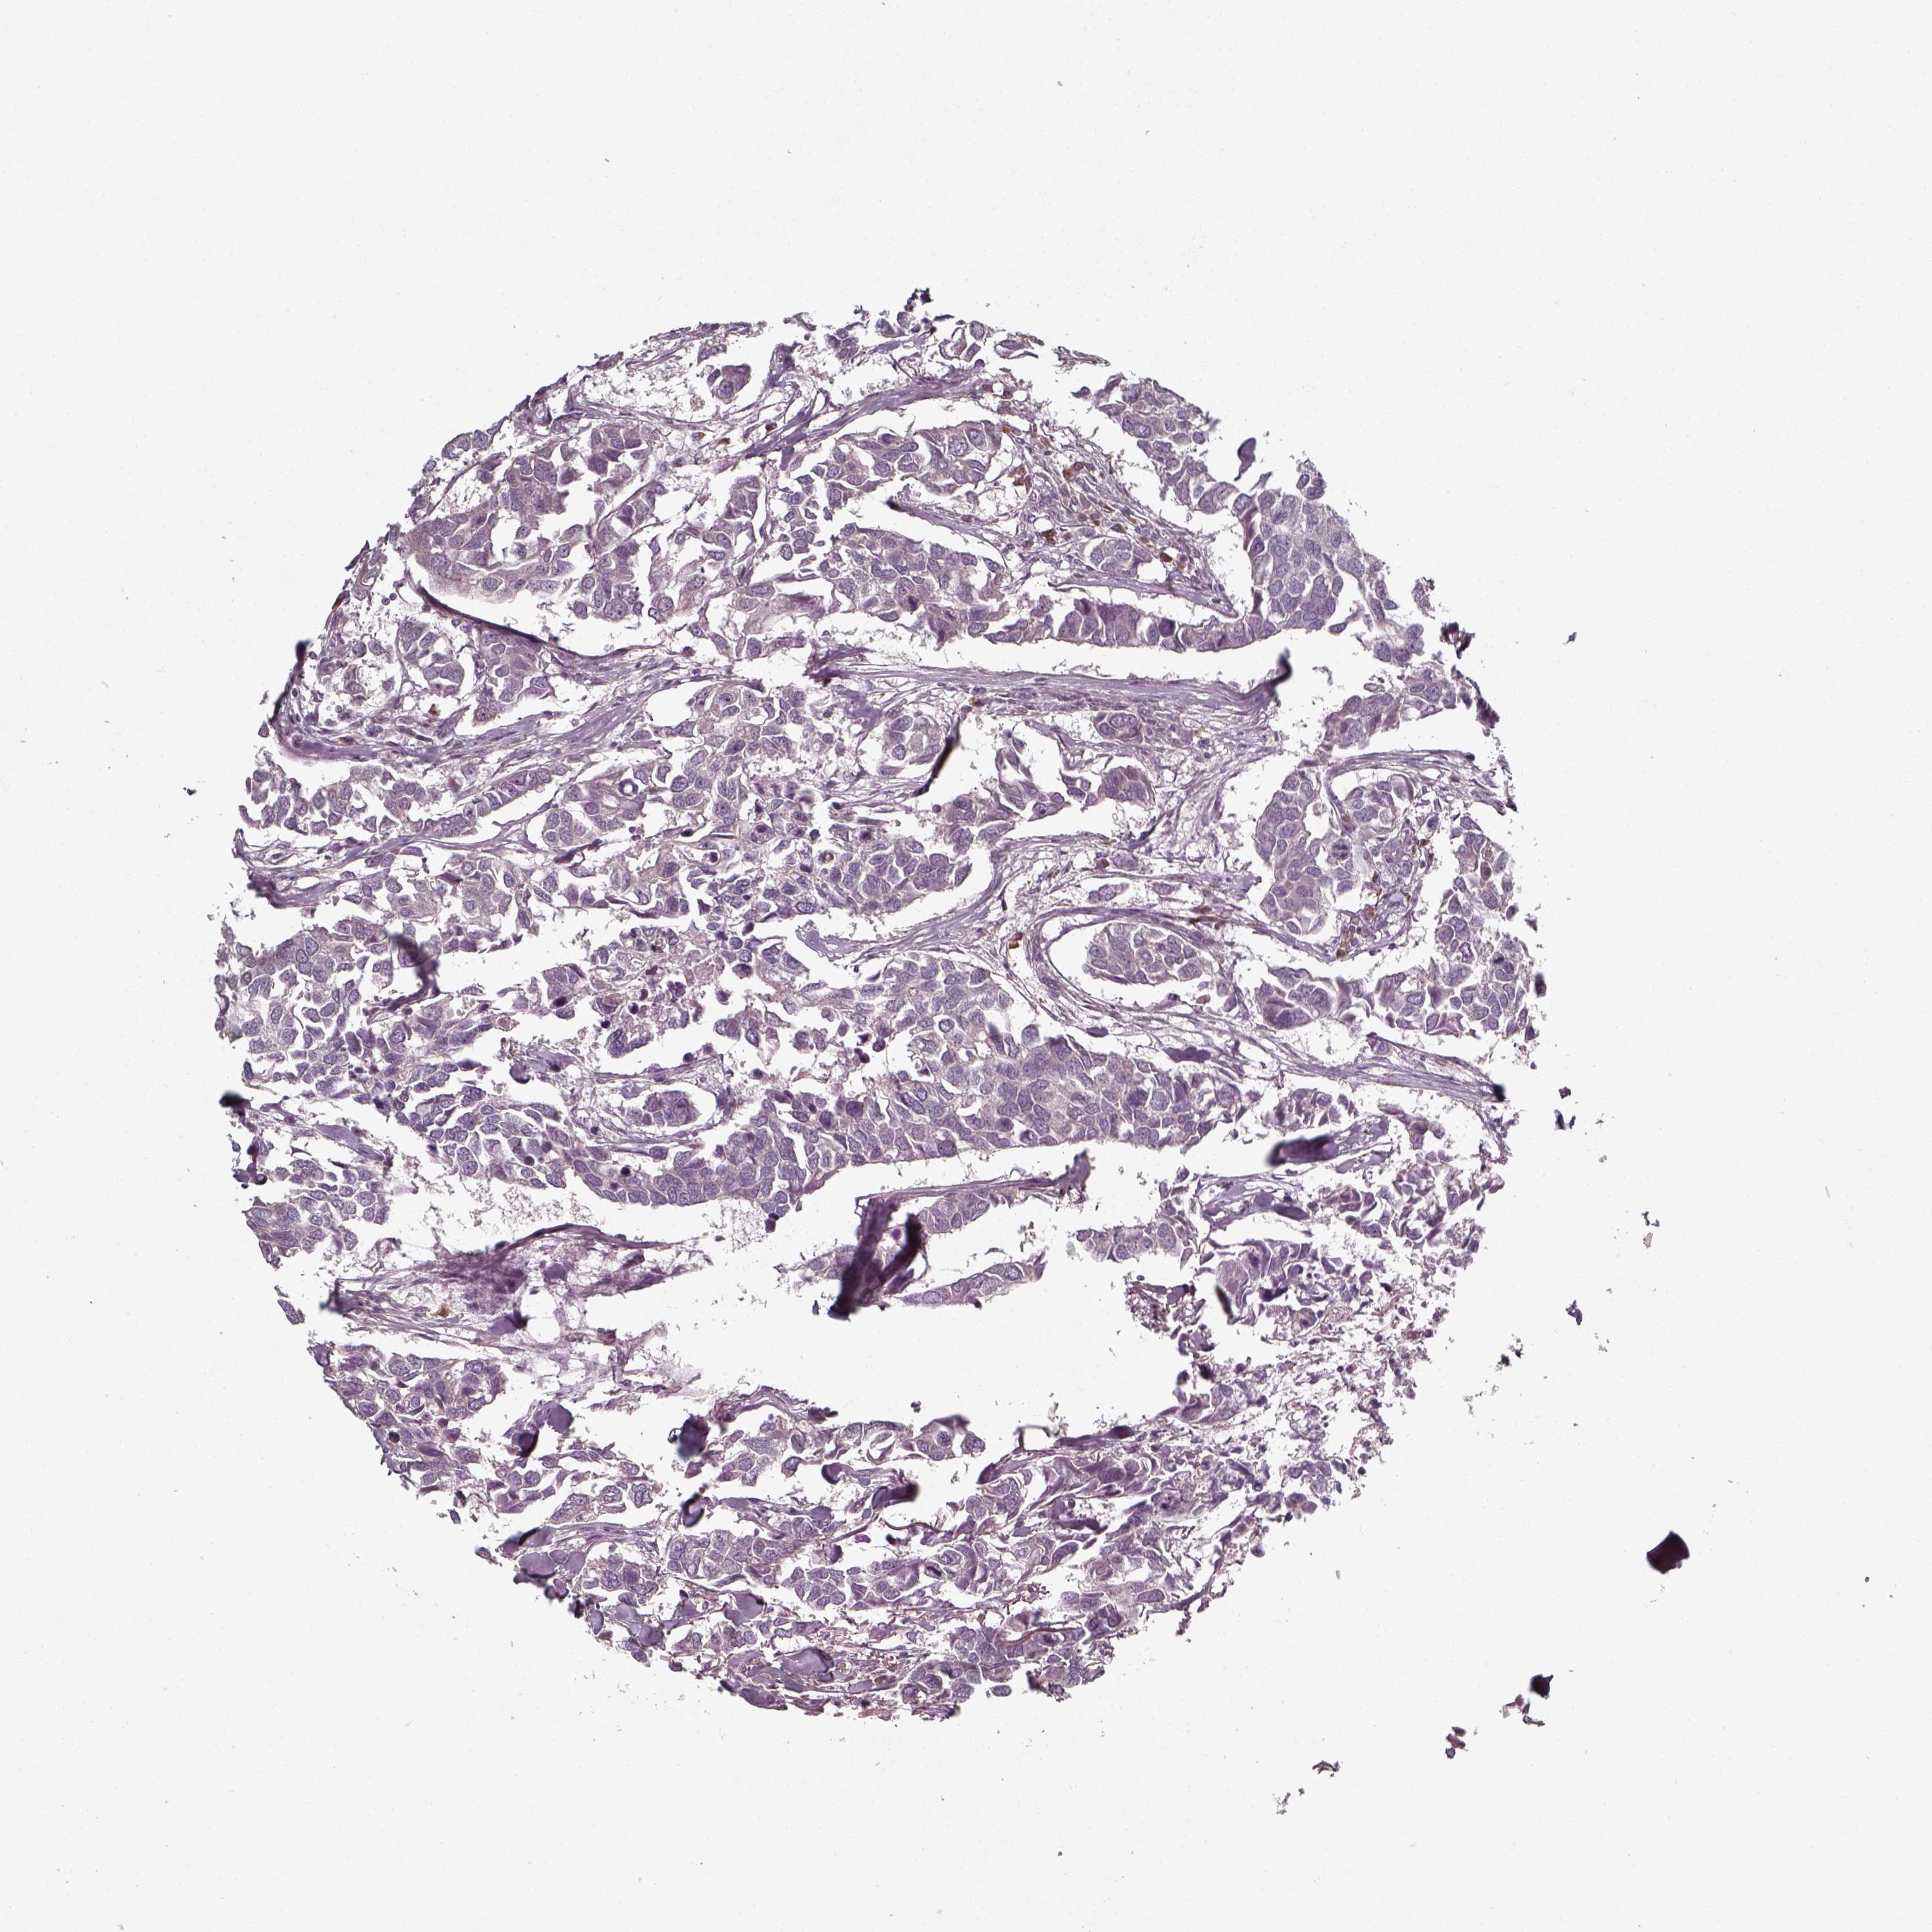

CANCER BREAST CANCER Show tissue menu

BRCA TCGA BRCA VALIDATION PROTEIN EXPRESSION